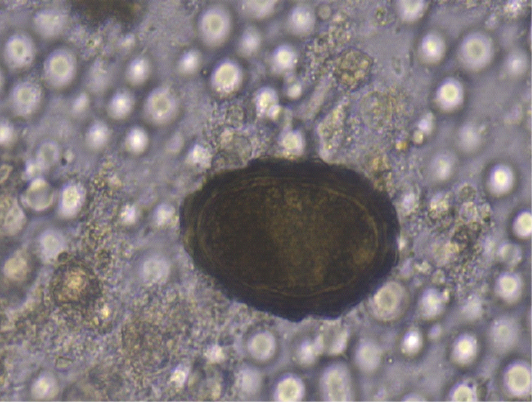

Figure 4

Ascaris suum egg (40x)